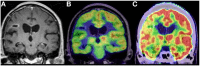

Advances in metabolic imaging techniques have allowed for more precise characterization of gliomas, particularly as it relates to tumor recurrence or pseudoprogression. Furthermore, the emerging field of radiogenomics where radiographic features are systemically correlated with molecular markers has the potential to achieve the holy grail of neuro-oncologic neuro-radiology, namely molecular diagnosis without requiring tissue specimens. In this section, we will review the utility of metabolic imaging and discuss the current state of the art related to the radiogenomics of glioblastoma.